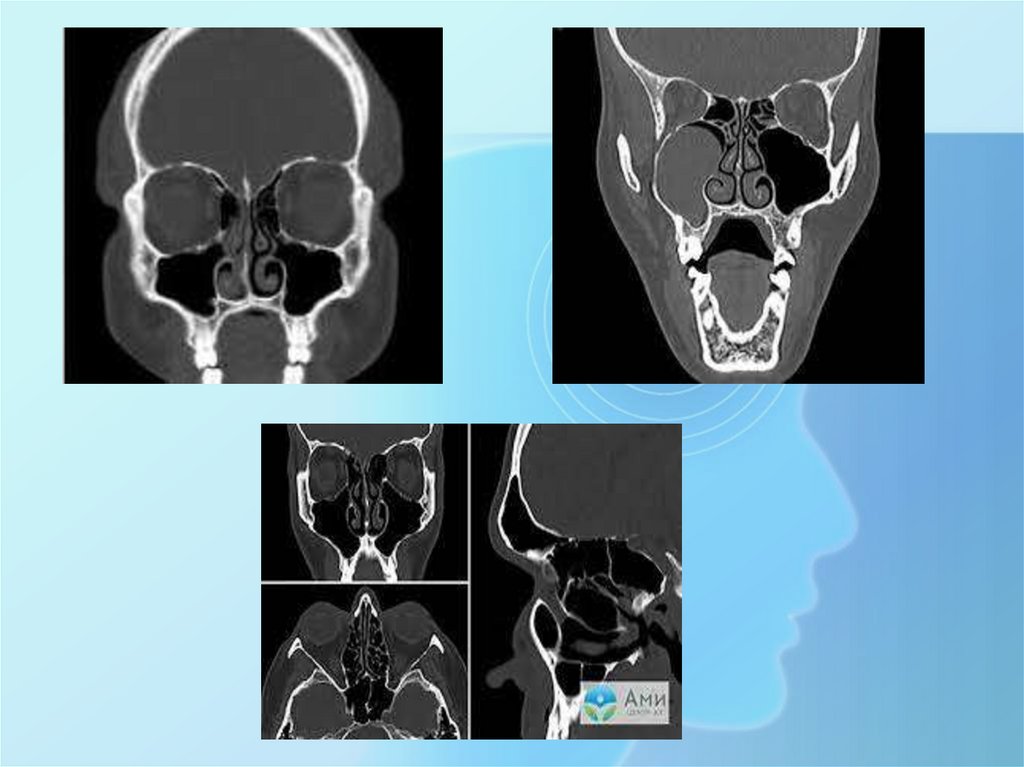

• Компьютерная Томография придаточных пазух носа — это

исследование, которое достаточно часто назначается ЛОР врачами и

является незаменимым методом при диагностике патологии всех

пазух и прилежащих структур, а также слезных протоков и соустий с

полостью носа.

• Показания к КТ придаточных пазух носа:

• острые и хронические воспалительные процессы в области носа

(гайморит, фронтит, этмоидит, сфеноидит);

• кисты и полипы пазух носа;

• подозрение на доброкачественные и злокачественные образования и

метастазирование;

• поражение слезных протоков и воспаление слезного мешка;

• травма лица и верхней челюсти, инородные тела;

• головные боли, при этом их причина не установлена;

• аномалии развитии;

• детализация анатомии и патологии перед проводимыми операциями

и манипуляциями в этой области.